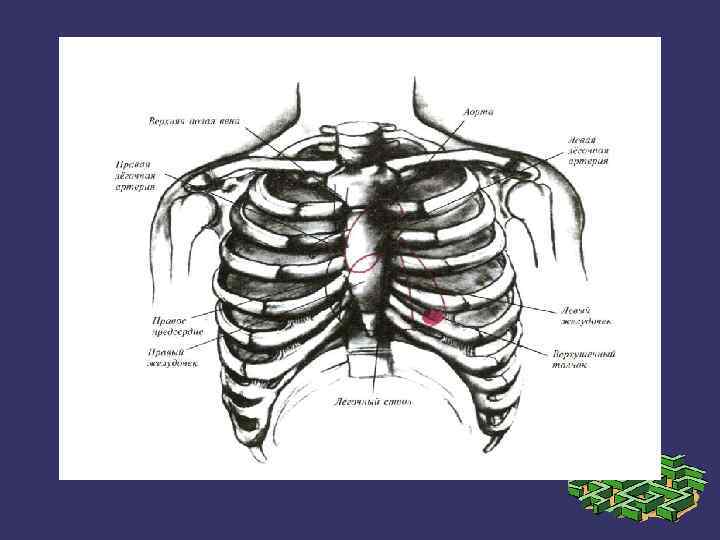

➲ ➲ ➲ Зерттеу барысында жүрек камераларының кеуде қабырғасына жатқызылуын елестетіп алуымыз керек. Оң жақ қарынша жүректің алдыңғы беткейінде орналасады. Бұл камера өкпе артериясымен кеуденің сол және артқы жағында сына тәрізді жазықтықты құрастырады. Оң жақ қарыншаның төменгі бөлігі кеуде денесінің төстің семсер тәрізді өсіндісімен байланысқан жерінен төмендеу орналасқан. Оң жақ қарынша жоғарыға қарай тарылады және III- қабырға мен төстің арасындағы шеміршек деңгейінде өкпе артериясына өтеді. Сол жақ қарынша оң жақ қарыншадан солға және артқа қарай орналасқан. Жүректің алдыңғы беткейінің кіші бөлігін ғана алып жатады. Клиникалық жағынан бұл өте маңызды, өйткені ол жұректің сол жақ бөлігін құрайды және жоғарғы серпілістің негізгі көзі болып табылады. Жоғарғы серпіліс бұл жүректің систола кезінде кеуде қабырғасына соғуын сипатайды және V қабырға арасында болады.

Митральды қақпақ (сол жақ жүрекше - қарыншалық қақпақ) төстің III қабырғамен түйіскен жерінде проекцияланады. Қолқа қақпағы төстің III қабырғаның сол және оң жақтарындағы шеміршектерінің бекіністерінің ортасынан жүргізілген сызықтың ортасында проекцияланады.

➲ Жоғары серпілістің перкуссиясынан кейін пальпациялық анықтауды өткізу керек – ол жүрек ұшының сол жақ бетіне сәйкес келеді. Жоғары серпіліс қалыпты жағдайда V қабырға аралық деңгейде 1 -2 см ішке қарай сол жақ ортаңғы бұғана сызығында орналасқан. Гипертрофия және сол жақ қарыншаның дилатация кезінде жоғарғы серпіліс қалыптастырғанда, оның локализациясы және негізгі сапасын өзгереді. Бұндай сапаға ені, биіктігі, күші және резистенттілігі жатады. Жүрек серпілісі қалыпты жағдайда пальпацияланбайды. Оң жақ қарынша гипертрофиясында ол төстің сол жағында пальпацияланады. Кеуде жасушасының пальпация кезіндегі тітіркенуі – “мысық миялауы“ жүрек ұстамасына тән болады. Аорта пульсациясы, эпигастриальды пульсация, бүйрек пульсациясы қалыпты жағдайда табылмауы керек.

Қорытынды Қорыта айтар болсақ зерттеу барысында жүрек камераларының кеуде қабырғасына жатқызылуын елестетіп алуымыз керек. Оң жақ қарынша жүректің алдыңғы беткейінде орналасады. Бұл камера өкпе артериясымен кеуденің сол және артқы жағында сына тәрізді жазықтықты құрастырады. Сол жақ қарынша оң жақ қарыншадан солға және артқа қарай орналасқан. Жүректің алдыңғы беткейінің кіші бөлігін ғана алып жатады. Клиникалық жағынан бұл өте маңызды, өйткені ол жұректің сол жақ бөлігін құрайды және жоғарғы серпілістің негізгі көзі болып табылады. Жоғарғы серпіліс бұл жүректің систола кезінде кеуде қабырғасына соғуын сипатайды және V қабырға арасында болады.